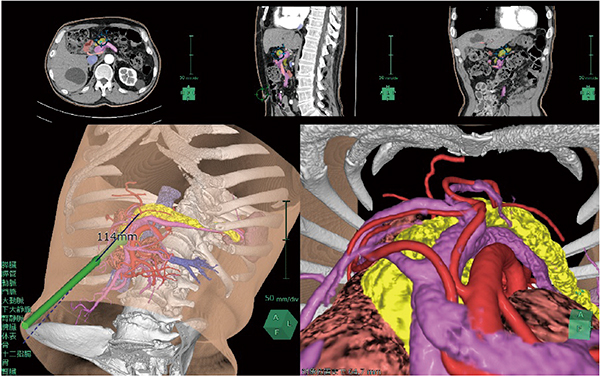

膵臓解析では,膵液の経路である膵管を自動で抽出する機能を搭載し,術前に膵管の位置を視覚的にとらえることができる。また,膵臓直交断面を表示することにより,指定位置での膵管の詳細な位置や膵実質断面の厚み,面積を計測することが可能である。加えて,ガイドライン1)で推奨されている門脈左縁での切除ラインの任意設定(図2)や,各膵腫瘍の位置に応じて腫瘍マージンを表示する機能(図3)を追加し,適切な切除ラインをプランニングするために必要な機能を提供する。切除ラインから残膵ボリューム(あるいは切除される膵臓ボリューム:図4)を算出し,体積評価も可能である。さらに,肝臓解析や腎臓解析と同様に,鏡視下シミュレータ(別途オプション必須)を連携して起動させることで,仮想内視鏡ビューを表示し,術前,術中に参照することができる(図5)。

図4 膵臓ボリューム計測